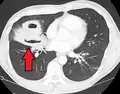

Pulmonary abscess on CT scan -

Lung abscesses are often on one side and single involving posterior segments of the upper lobes and the apical segments of the lower lobes as these areas are gravity dependent when lying down. Presence of air-fluid levels implies rupture into the bronchial tree or rarely growth of gas forming organism.